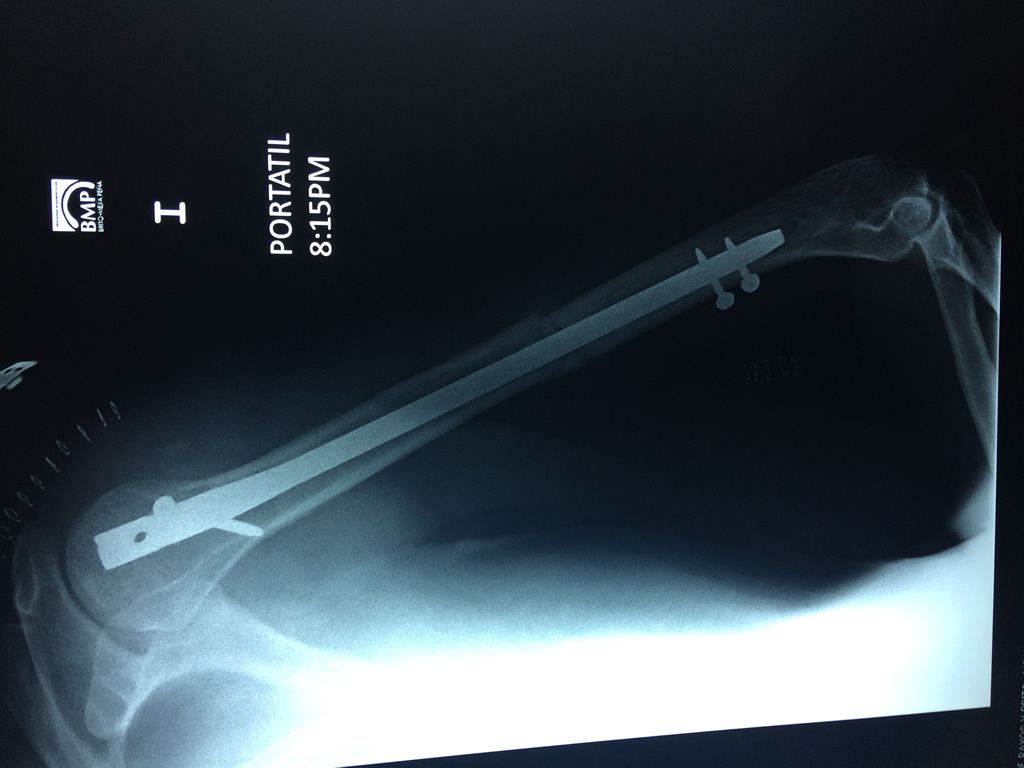

Cirugías de Codos - Húmero

El Húmero (en latín, humerus) es el hueso más largo de las extremidades superiores en el ser humano. Forma parte del esqueleto apendicular superior y está ubicado en la región del brazo. ... El extremo proximal del húmero tiene la cabeza, cuellos quirúrgico y anatómico y tubérculos mayor y menor.